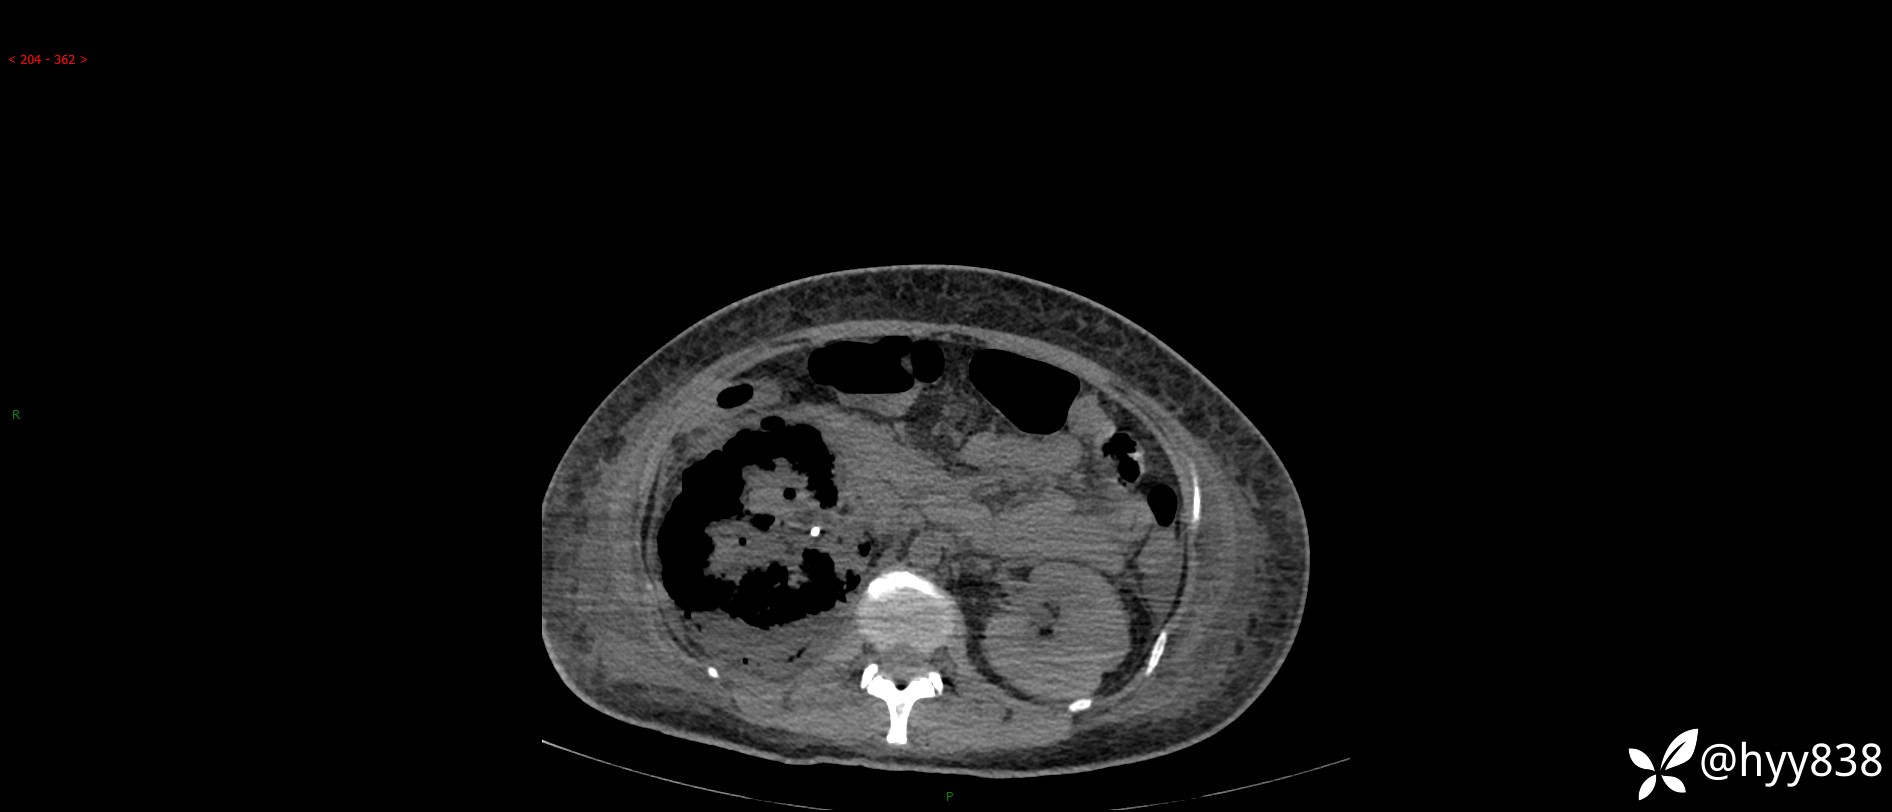

大年三十︱年轻女性,饮酒后突发腰痛,很意外---结果公布~

患者年龄:29岁

主诉:右侧腰部疼痛2天

简要病史:患者2天前和朋友聚餐饮酒时出现右侧腰部疼痛不适,呈间断性胀痛,伴发热、呕吐,无头晕、心慌、胸闷等不适,不伴有尿频、尿急、尿痛等症,院外与当地诊所输液对症治疗症状未见明显改善,今来我院急诊就诊全腹部CT自阅片考虑右肾周围炎,现患者为寻求进一步就诊,来我科就诊,我科以“右肾周围炎”收治入院。 起病以来,患者精神、饮食、睡眠可,大小便正常,体力体重无明显减轻。

临床诊断:肾周围炎

肾脏CT平扫